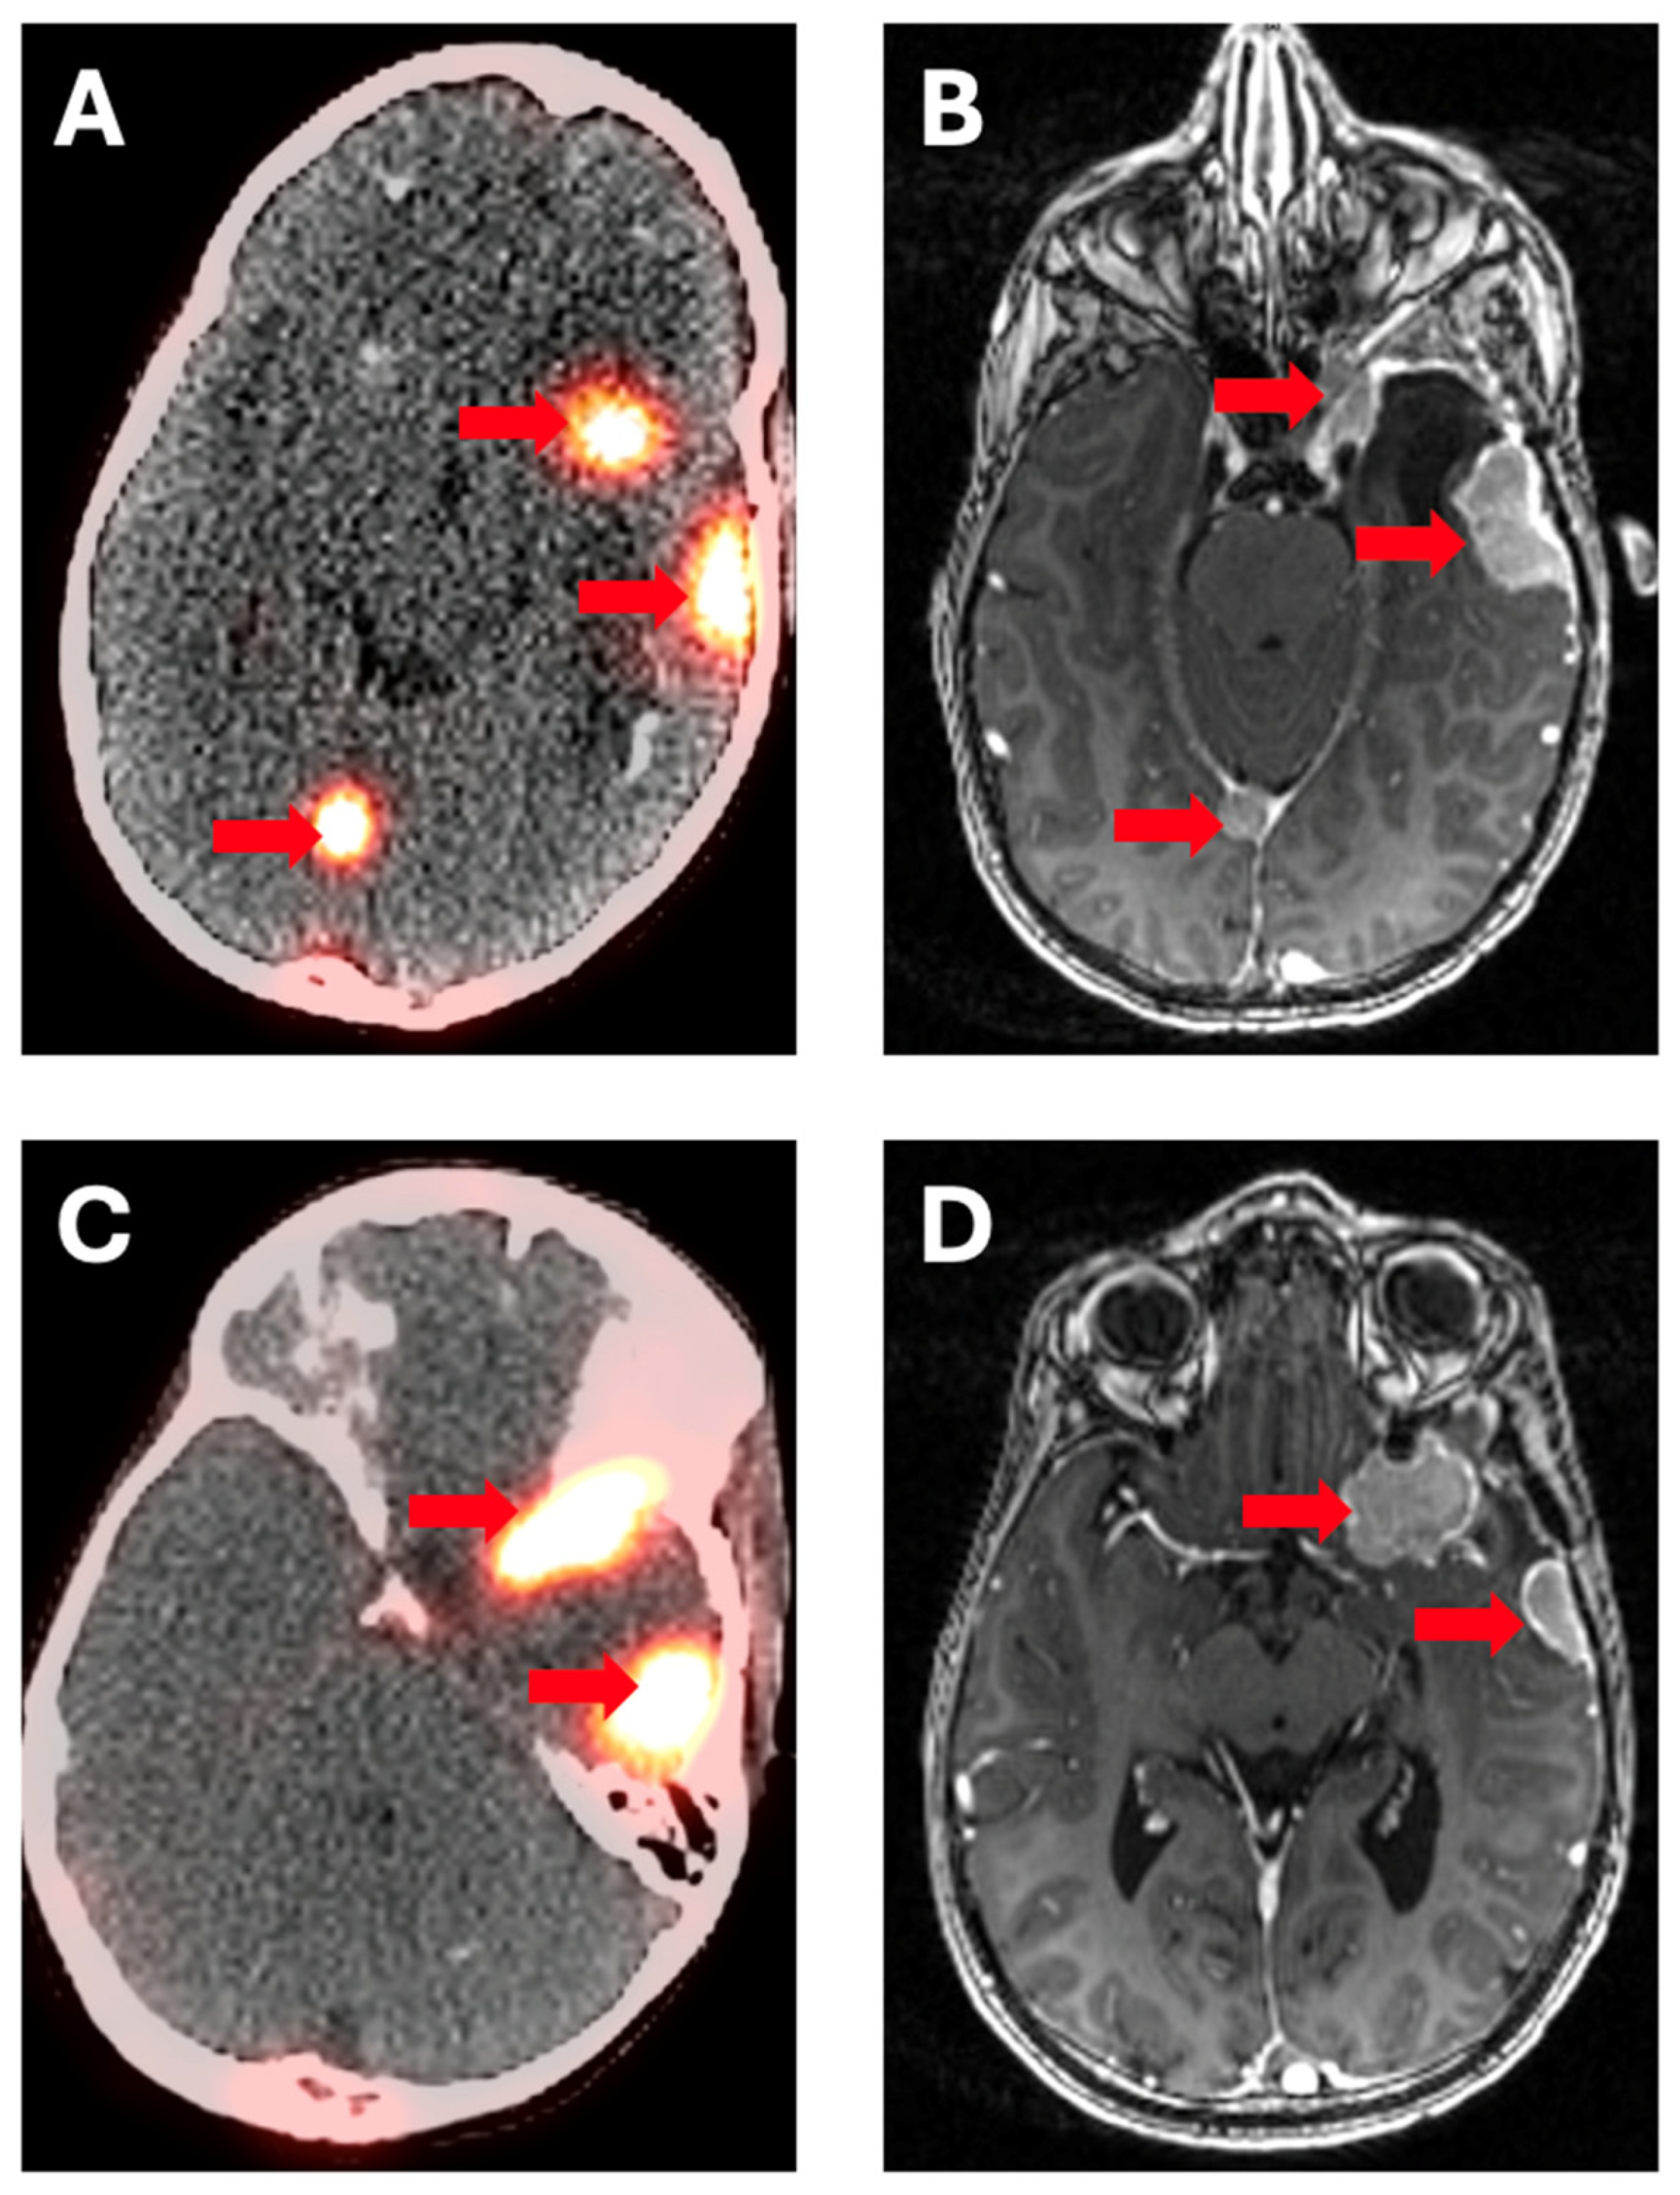

4. Somatostatin Receptor Inhibitors (DOTATATE)